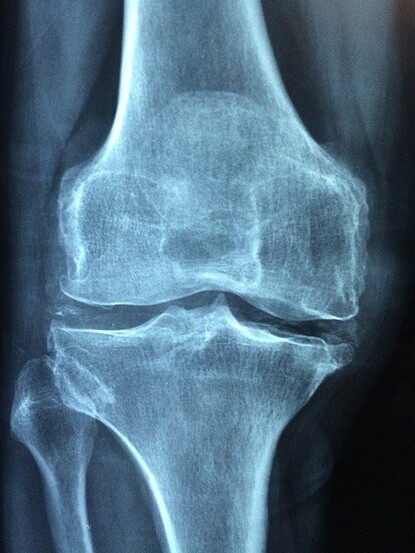

Il y a sûrement quelqu’un dans votre entourage qui souffre de fragilité osseuse ou d'ostéoporose. C’est un mal très répandu et, même si beaucoup de gens sont attentifs à ne pas souffrir de carence en calcium - les uns en se gavant de lait, d'autres en consommant des compléments - cela ne marche pas si bien, les problèmes subsistent et d'autres, en revanche, apparaissent...

Le calcium a la faculté de se déposer un peu n'importe où, comme un dépôt de tartre, s'accumulant dans les trous et s'accrochant aux aspérités. Il paraît que les médecins qui font des autopsies sur les personnes âgées, constatent que certains tissus ont complètement perdu leur souplesse et qu’ils peuvent parfois être durs comme de la pierre. Cela semble normal finalement puisque de nombreuses maladies liées à l’âge, peuvent être attribuées à la calcification des tissus.

On pense immédiatement aux vaisseaux, qui se durcissent en vieillissant, mais il s’agit également de calcification lorsqu’on parle de calculs rénaux, d’arthrite, de cataracte, de sénilité et même de peau ridée. Le calcium, il faut donc s'en méfier, mais dans le même temps l’homme perd en moyenne 20% de son capital osseux entre 20 et 60 ans et la femme 40% (le moment de la ménopause accélère brutalement la perte). Et pour ralentir la dégradation il faut donc apporter quotidiennement du calcium au corps. Difficile équation à résoudre